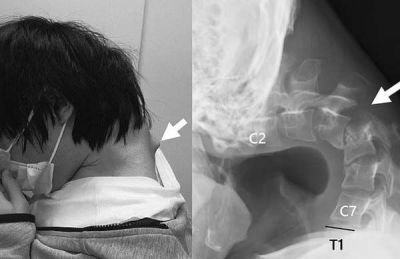

스스로 머리를 들어 올릴 수 없을 정도로 목뼈가 꺾이는 이른바 '머리떨굼 증후군' 진단을 받은 일본 20대 남성의 사연이 알려져 충격을 던졌다. 이 남성은 10대 초반부터 하루에 몇 시간씩 스마트폰 게임을 한 것으로 알려졌다.

의료진은 "고개를 숙인 채 오랜 시간 스마트폰 게임을 하면서 목의 척추뼈가 탈구(뼈가 제자리를 이탈하는 현상)됐다"며 "환자의 목 뒷부분에 흉터처럼 혹이 튀어나왔는데, 비정상적인 자세 때문에 척추뼈가 극도로 늘어난 결과"라고 말했다.

이에 의료진은 우선 목을 고정하는 의료 기기를 이용해 교정을 시도했다. 그러나 남성이 감각 이상을 호소하면서 결국 목뼈에 나사와 금속 막대를 삽입하는 수술을 진행했다.

수술 후 6개월 만에 이 남성은 머리를 수평으로 유지할 수 있게 됐고, 1년 뒤 추적 검사에서 머리떨굼 증후군 증상이 재발하지 않은 것이 확인돼 일상으로 돌아올 수 있었다.